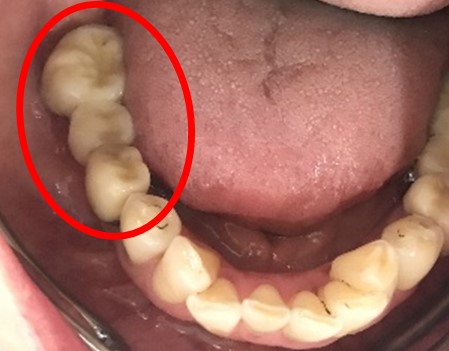

以前、1本歯がないところを、欠損の両側に被せ物をしてつないだブリッジでした。その2本のうちの前方の歯が歯根の破折を起こし、抜歯になり2本の欠損になりました。この2本の欠損を補う方法には、部分入れ歯、再度ブリッジ、インプラントの3つの方法があります。部分入れ歯もブリッジも欠損部分の負担をほかの歯に負わせるため、支台になった歯は負担が大きくなり、虫歯、歯周病、歯根破折の危険性が高まり、さらに歯を失うことになります。インプラントは、それ自身が単体で植立しているため他の歯に負担を負わすことがありませんので、咬合を回復させるだけではなく、他の歯を守る役割もあります。今回もX-Guideを使った埋入で、安心安全に行うことできました。

インプラント2本:¥363,000×2本=¥726,000(税込)

Before

After